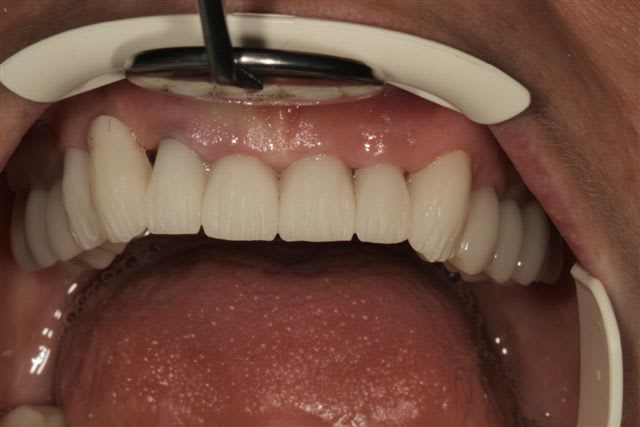

La suite, les soins ont commencés le 07/08.

Postérieur bas (16/08)et haut (14/09) en place, essayage des Emax avec "cutback".

Pour la teinte la patiente exige B1, sans maquillage, elle n'a pas attendu 47 ans pour que ça ne soit pas Blanc de blanc, alors là dessus j'ai cédé.

Cas typique de patient refusant l'ortho avant la réhabilitation global, avec un résultat esthétique ....disons que j'aime pas, bon si la patiente est contente!

Moi en tout cas au prochain patient qui refuse l'ortho nécessaire avant la réhabilitation globale, je lui montre ce cas. Merci encore je pense que cela sera utile.

Peut-on encore à ce stade diminuer (fortement) le volume des canines, réaligner les faces vestibulaires des PM droites, augmenter le volumes des centrales et distaliser les latérales???

Une petite élongation coronaire sur 11 et 21 n'aurait pas été de refus si racine pas trop courte.

1) la patiente a une paralysie faciale (levre superieure gauche). Le fait que les canine-premolaires-molaires cote II soient plus longues que les incisives accentue ce probleme.

Je raccourcirais ttes les dents de 23 à 26 de 2mm.

2) Axe de 13 pas bon. trop de bombe vestibulaire. Peut etre que la dent n'est pas assez taillee. En tout cas je la trouve trop dominante dans le sourire.

09/10/2012 à 19h11

Les 2 canines sont effectivement très massives... Après tu fais avec les moyens que la patiente te donne, évidemment, mais là pour le coup je trouve pas ça très beau non plus.